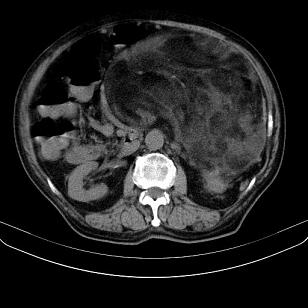

标题: CT21671:男,88岁,左上腹包块 [打印本页]

标题: CT21671:男,88岁,左上腹包块

患者因咳嗽而住院,自觉右上腹包块,无其他不适。

腹膜后脂肪肉瘤

小网膜脂肪肉瘤。

左侧腹膜后脂肪肉瘤。